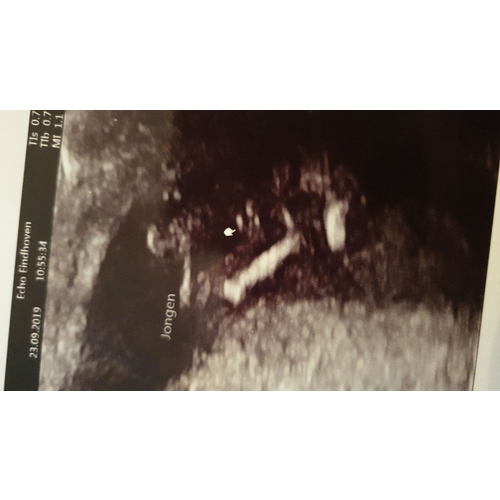

Wij hebben de echo met 15,5 week gedaan en het is overduidelijk een jongen. Ik had al eerder over meiden gelezen die twijfelde na de echo en toen gaf iemand de tip om diegene vanuit meerdere hoeken het te bekijken. Dat deed de vrouw die de echo maakte gelukkig uit zichzelf al. Maar dat ga je wel meer een zekerder gevoel weg daar. Wij hebben de echo overigens bij een echocentrum laten maken die ook medische echo’s doen en ze heeft allerlei dingen al van de 20 weken echo bekeken. Was ook super fijn!